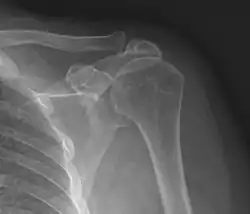

Plain x-rays of the shoulder can be used to detect some joint pathology and variations in the bones, including acromioclavicular arthritis, variations in the acromion, and calcification. However, x-rays do not allow visualization of soft tissue and thus hold a low diagnostic value.[2] Ultrasonography, arthrography and MRI can be used to detect rotator cuff muscle pathology. MRI is the best imaging test prior to arthroscopic surgery.[2] Due to lack of understanding of the pathoaetiology, and lack of diagnostic accuracy in the assessment process by many physicians,[21] several opinions are recommended before intervention.

Plain x-rays of the shoulder may show a “proximal humeral pseudocyst”. This localized area of bone atrophy is the result of increased blood circulation which demineralizes the bone at the attachment of the rotator cuff tendon. It is evidence of chronic inflammation of the rotator cuff. Chronic shoulder inflammation is frequently asymptomatic, and this cystic appearance may be the only evidence of an inflammation.[22][23]